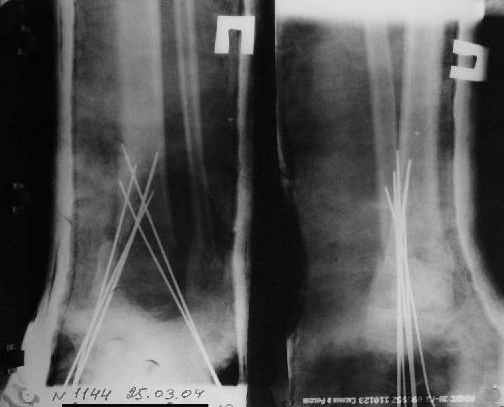

Фиксация

в гипсе